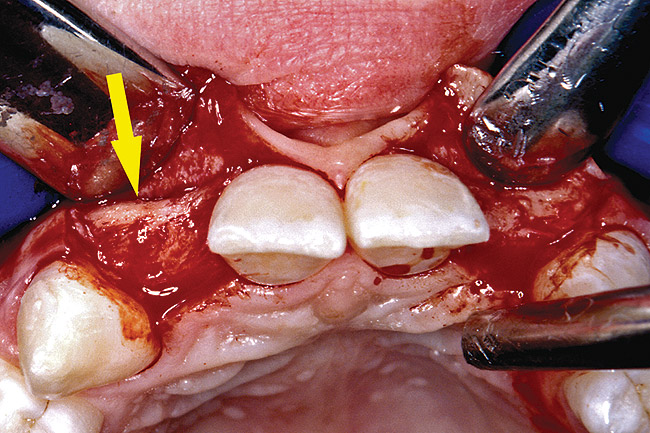

Before the day of surgery, the patient was seen by the orthodontist for the removal of the orthodontic brackets. The patient still was not pleased with the position of the two centrals, and it was determined that this would be addressed after implant placement (Figure 26). The anatomical variations of the crestal tissue and lack of interdental papilla can be appreciated in the close-up views of the right and left sites (Figure 27 and Figure 28). There were no surprises on the day of surgery as all of the decisions were made during the planning phase, before the scalpel ever touched the patient. The occlusal view of the CT 3D model revealed the wider alveolar ridge on the right side and thinner crest on the left side (Figure 29). This was confirmed when the full-thickness mucoperiosteal flaps were elevated, and the underlying bone revealed (Figure 30). The tooth-borne templates were designed to facilitate the drills and drilling sequence specific to the diameters of the predetermined implants (Figure 31). Each template contained an embedded 5-mm long stainless steel tube, which was approximately 0.2-mm wider than each drill (just wide enough to allow for the drills to rotate freely). Once positioned over the natural teeth, the template was secure and offered precision accuracy in transferring the implant locations from the original software-designed plan, allowing the potential for internal and external irrigation (Figure 32).

Figure 29  VIRTUAL PLANNING AND SURGERY The information gained from the 3D model was confirmed when the flaps were elevated.

Figure 29

Figure 30  VIRTUAL PLANNING AND SURGERY The information gained from the 3D model was confirmed when the flaps were elevated.

Figure 30